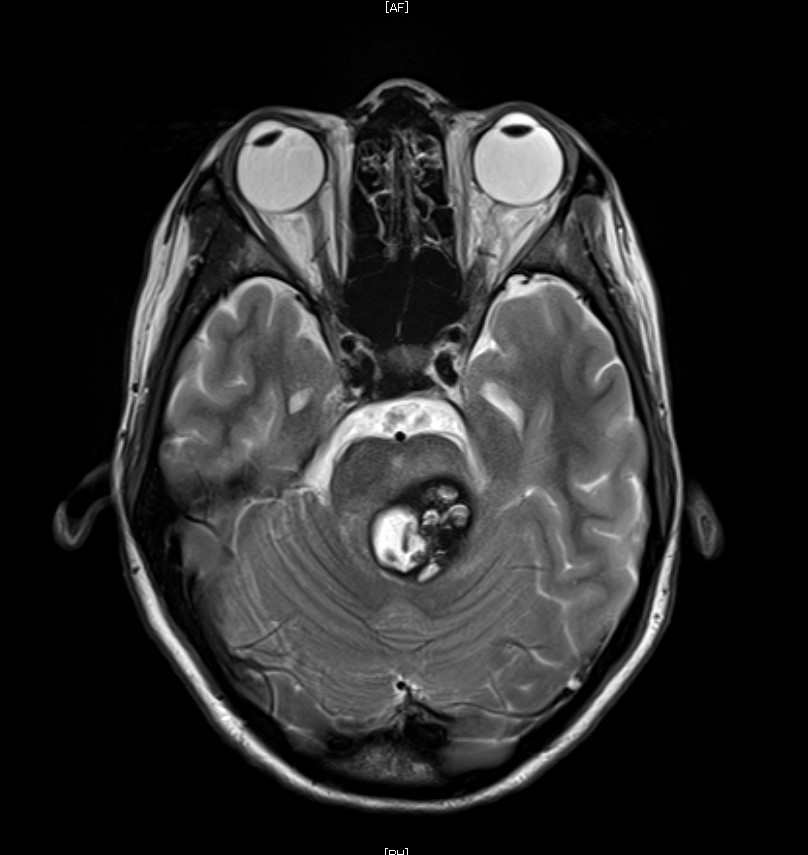

脳幹部海綿状血管腫のMRI

海綿状血管腫は、血管奇形の一つです。最近は脳ドックで見つかることが多い病気で、ほとんどの場合は無症状です。無症状の海綿状血管腫は、長期的に安定しており経過観察が基本的な治療方針です。しかし出血や、海綿状血管腫そのものにより脳が圧迫され神経症状が出現した場合や、てんかんの原因になった場合には手術による切除を考慮します。多発性、家族性のものもあります。多くは大脳にできますが、脳幹部にできる海綿状血管腫は出血しやすいことが知られています。脳幹部海綿状血管腫の出血では眼球運動障害や手足や顔面の麻痺、感覚障害や顔面神経麻痺など重篤な症状をきたすことがあります。しかし、手術も大きなリスクを伴うため、十分に検討する必要があります。

静脈性血管腫は脳血管の形成異常ですが、これは出血するリスクは非常低いもので、治療の適応になることはほとんどありません。海綿状血管腫と合併することが多く、手術の際に傷つけると静脈梗塞を合併するリスクがあります。